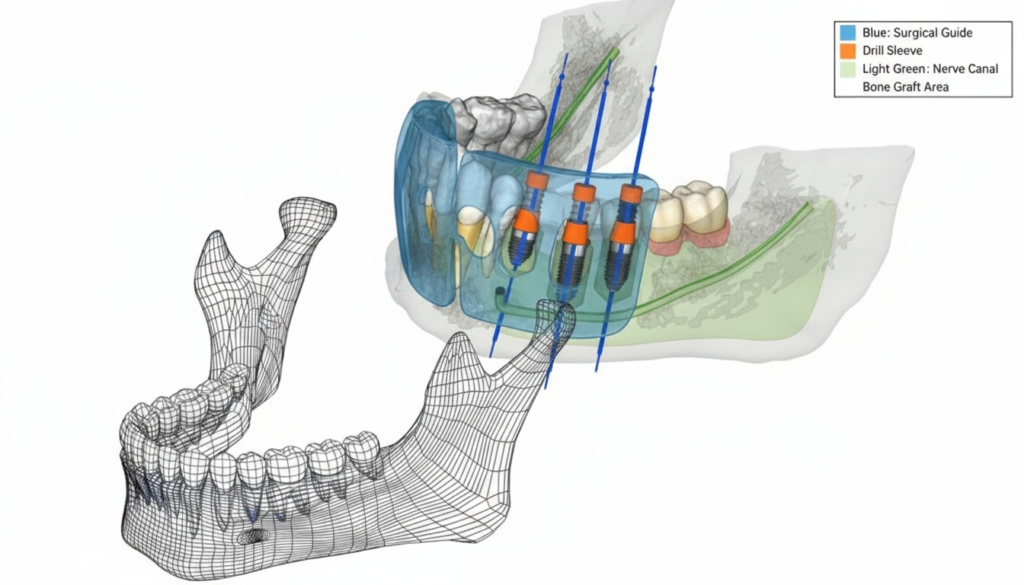

インプラントガイド

インプラントガイドは、インプラント治療を「正確」「安全」「スムーズ」行うための重要なサポートツールです。

手術時にインプラントを埋入する深さや角度を正確にナビゲーションしてくれます。このガイドに基づいて手術を行うことで、 人為的な誤差を大幅に減らすことができます。

ガイドシステム採用

顎骨は細いため、角度により顎骨からインプラント先端が出ることがあります。当院ではガイドシステムを採用しているため、経験や勘に頼らない精密な手術が可能です。その結果、口腔内の傷口も最小限のとどめることができ、術後のダウンタイムも少なく済みます。

ガイドシステム採用

顎骨は細いため、角度により顎骨からインプラント先端が出ることがあります。当院ではガイドシステムを採用することにより、経験や勘に頼らない、精密な手術ができることのより、口腔内の傷口も最小限のとどめる為術後のダウンタイムが少なく済みます。